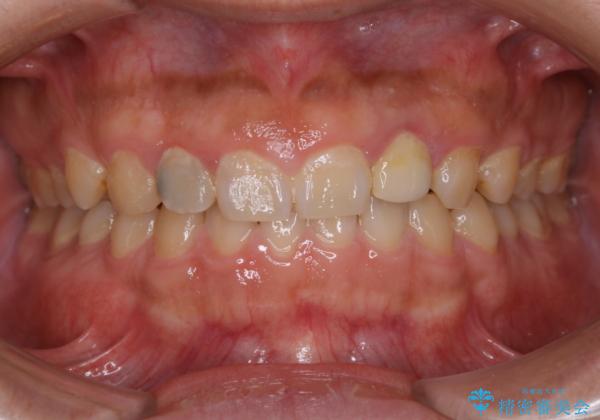

- 全体的にクリーニングをして欲しいとのことで来院されました。

PMTC60分コースを行いました。

20年ぶりのクリーニングということもあり、歯の表面全てにプラークが付着していました。

プラークの細菌によりかなり歯ぐきが腫れていました。1度のクリーニングで汚れは落とせますが、このまま何もしないとまた同じようにプラークが付着し、それを繰り返すことになるだけでなく、歯周病や虫歯が進行してしまいます。そうならないためには、日々のケア、ホームケアがとても大事になっていきます。